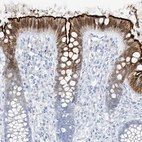

Immunohistochemistry analysis in human colon and skeletal muscle tissues using HPA036055 antibody. Corresponding SLC26A3 RNA-seq data are presented for the same tissues.